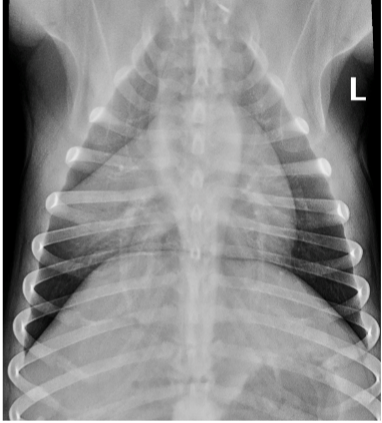

• what pattern is seen in this image?

alveolar

• alveolar infiltrate = patchy / focal

For diagnosis, radiographs can be taken, and in these cases there will be alveolar infiltrate (patchy/focal). The most common affected lobes are right middle, right cranial and left cranial.